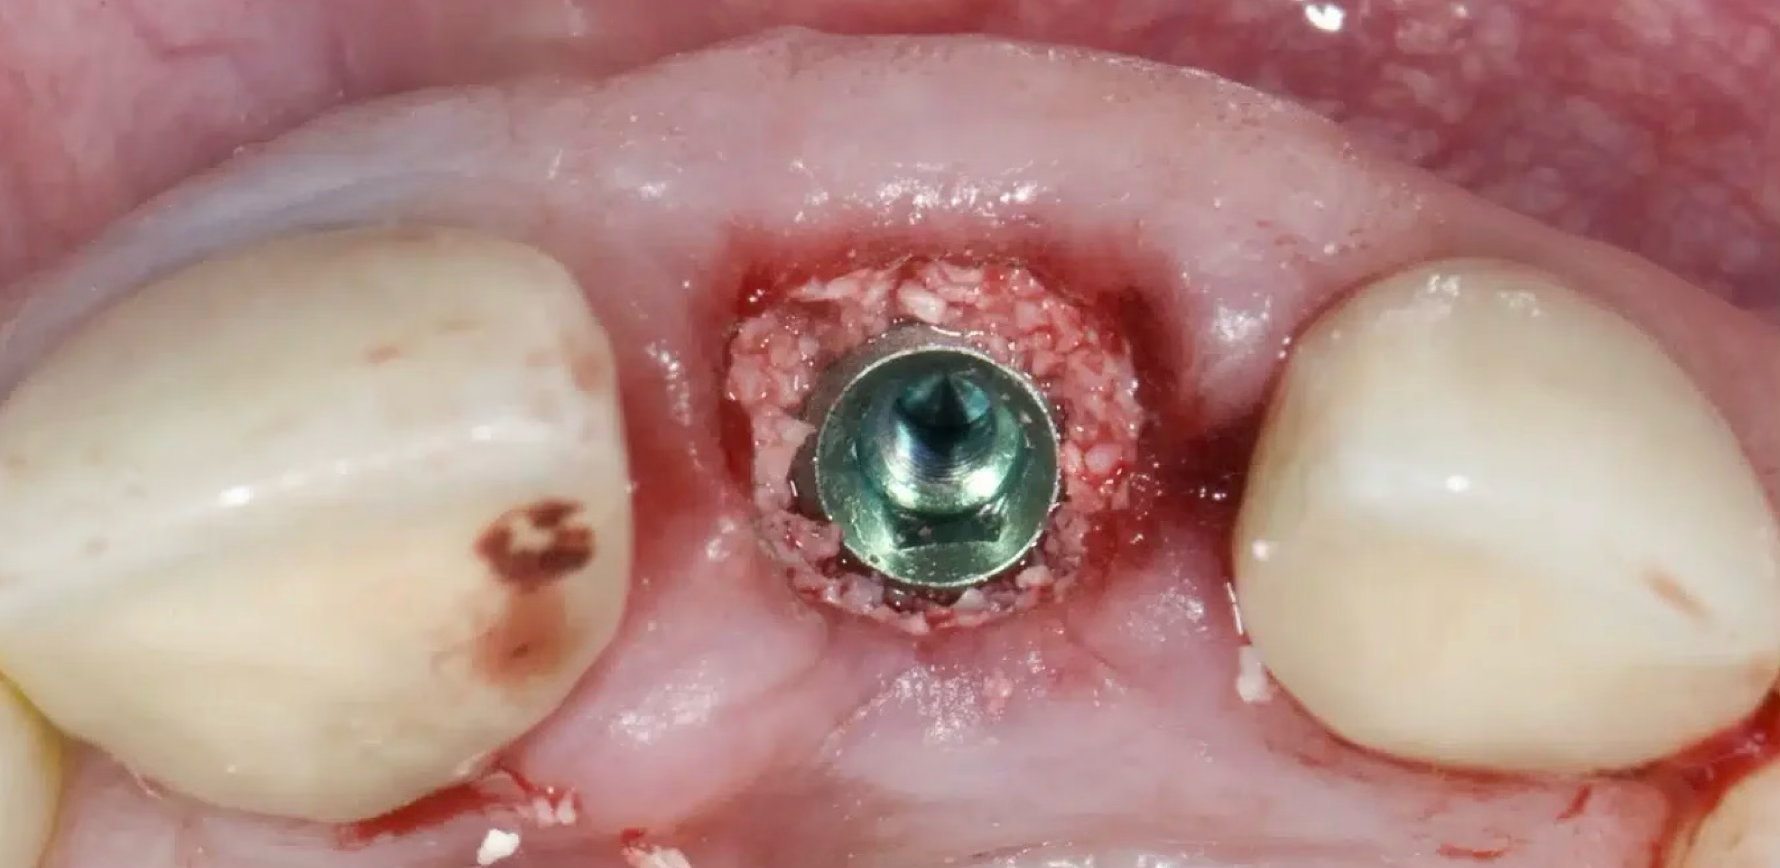

3단계: 임플란트 식립

임플란트와 발치소켓 사이 여유공간

4단계: 뼈이식 완료

빈공간에 뼈이식재로 완벽하게 채워진 상태

중요: 1-2mm 이상의 간격(gap)는 반드시 뼈이식이 필요합니다

- ✓발치소켓과 임플란트 사이의 빈공간은 자연치유가 어려움

- ✓뼈이식을 통해 안정적인 골유착과 임플란트 성공률 향상

- ✓적절한 뼈이식으로 장기적인 안정성 확보